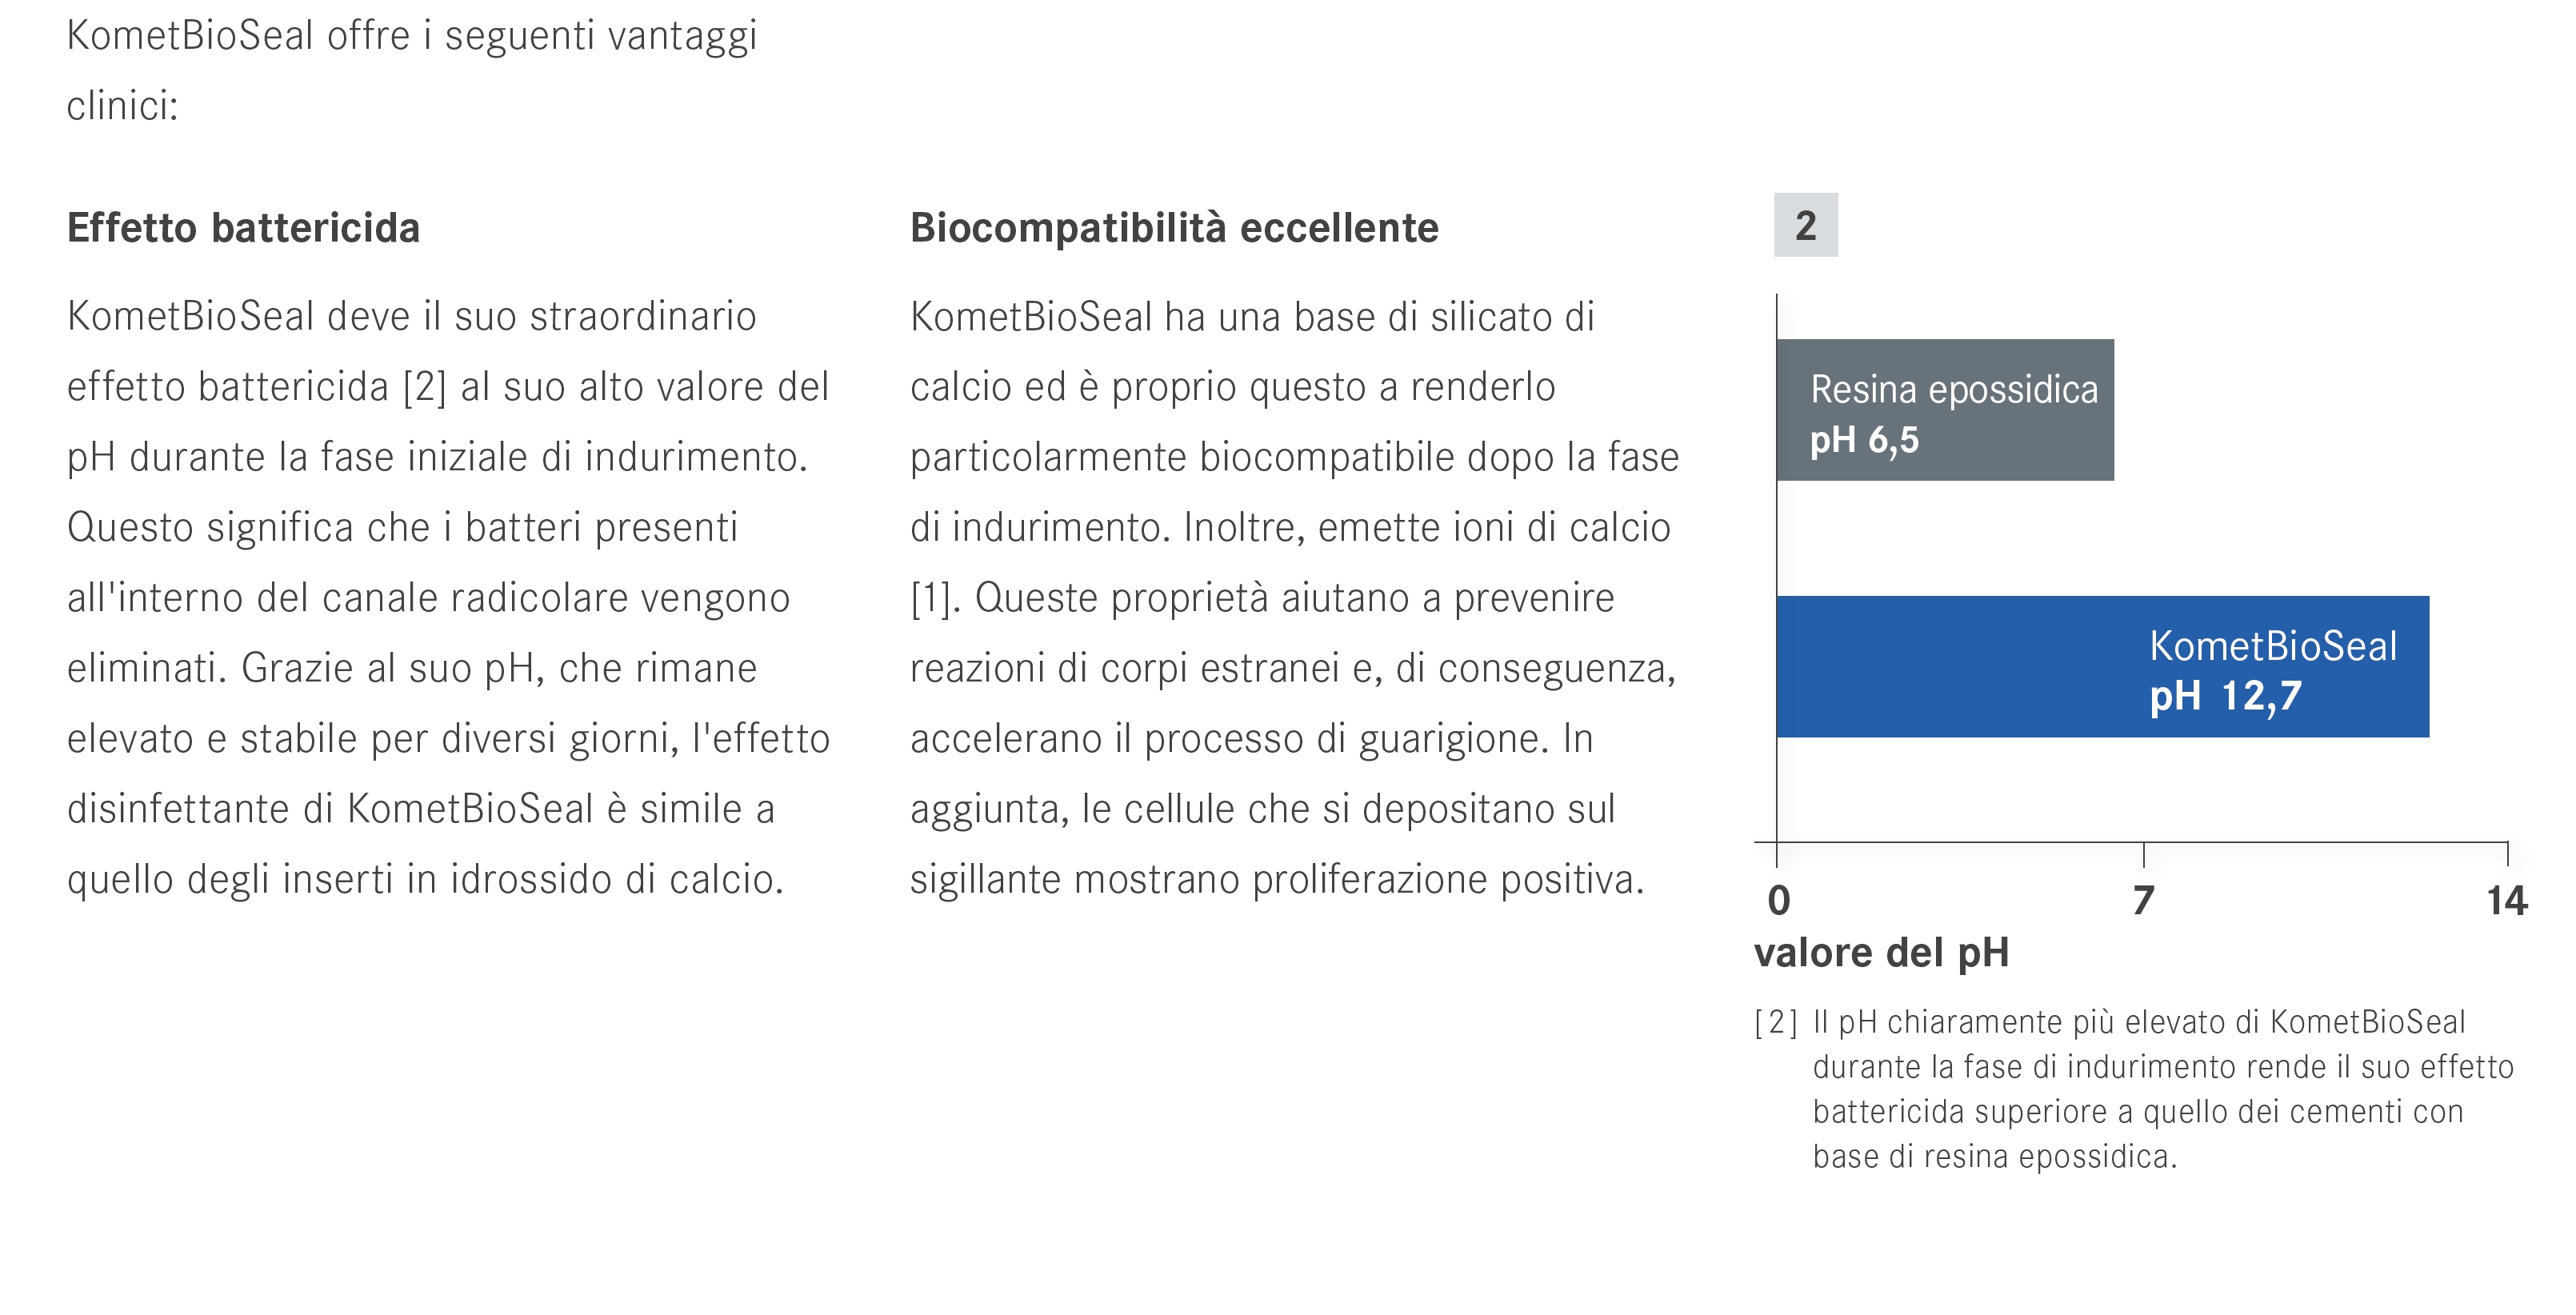

La chiusura è effettuata con cono singolo e bioceramico Komet BioSeal.

Trattamento endodontico di un incisivo laterale superiore con due radici - parte 12La chiusura è effettuata con cono singolo e bioceramico Komet BioSeal.